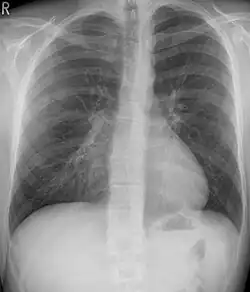

Pleural effusion

A pleural effusion is an accumulation of fluid inside the pleural space. If this collection of fluid gets large enough, it can also push structures in the chest away from it and cause a mediastinal shift. However, a pleural effusion can also pull the mediastinal structure towards itself. If this is the case, then there is an underlying condition causing the collapse of the lung on that side. An example is a tumor obstructing a bronchus and causing lung collapse and pleural effusion.[3]